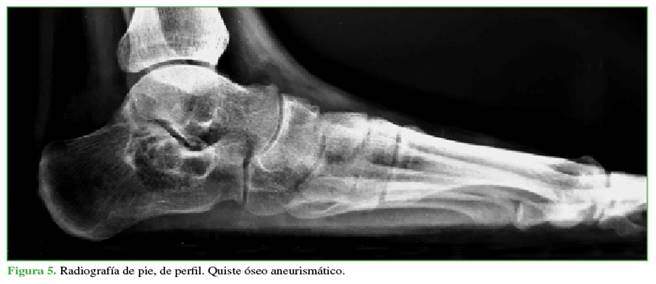

Se planteó el diagnóstico diferencial de tumor benigno polilobulado de calcáneo entre quiste sinovial simple óseo (Figura 4), QOA (Figura 5) o lipoma intraóseo (Figura 6).